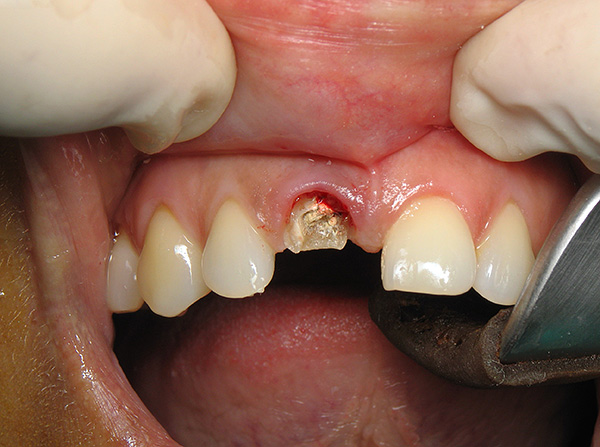

- Con fratture complesse del dente (ad esempio, con una longitudinale - vedi l'esempio nella foto sotto);

- Sullo sfondo di gravi processi infiammatori vicino alla radice (grande cisti, periostite, osteomielite, ascesso, flemmone);

- La distruzione della corona del dente è molto più bassa del livello delle gengive;

Tuttavia, come già notato sopra, lontano da ogni frattura del dente, le radici rimanenti devono essere rimosse. Una scheggia può dividere sia da un dente vivo che da un dente morto, cioè precedentemente depulso, e i morti sono più vulnerabili a questo proposito, poiché diventano fragili nel tempo. Quindi, se la radice non è molto colpita e ha una solida base, il dente viene ripristinato con metodi convenzionali: il canale viene trattato (se il dente era vivo) e la corona viene ripristinata mediante restauro o protesi.